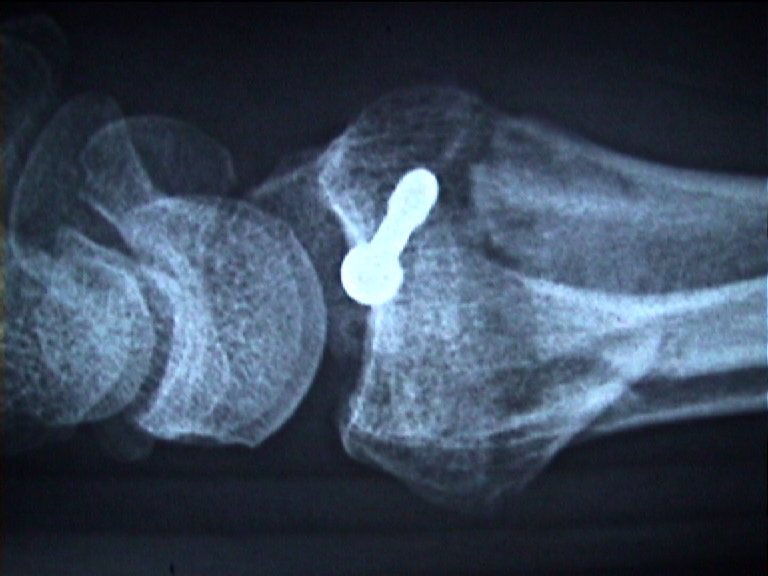

Arztbrief